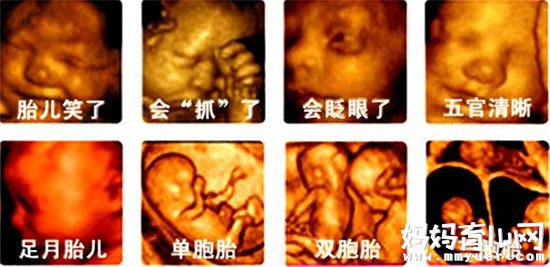

可以明确的是,四维彩超确实能够看到胎儿的性别。因为四维彩超和其他超声检查相比,它能够显示宝宝的实时动态活动,也能够准确的分辨出胎儿的性别。

四维彩超怎么看性别

通过四维彩超看性别,如果是没有没有经过训练的话,一般是看不出来的,及时让你看见了图像,也可能看错。所以必须要有经验丰富的医生来看,这样准确率才更高。但是,由于国家禁止性别检查,所以医生其实不会告诉你结果。如此一来,有人就又说了,还可以通过四维彩超的数据来看性别。